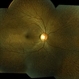

- Fundus Albipunctatus

- Fundus albi